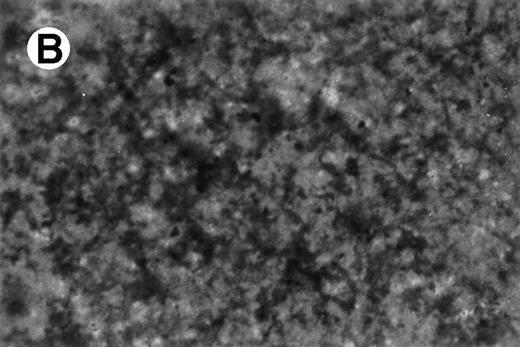

UG3 cells preincubated with 100 ng/mL M-CSF for 2 weeks formed multinucleated giant cells displaying TRAP activity when cultured for an additional 2 weeks in the presence of both 100 ng/mL M-CSF and 100 U/mL IL-4 (Fig10). UG3 cells did not form multinucleated giant cells when cultured with M-CSF alone for the whole observation period of 4 weeks (not shown). UG3 cells cultured in osteologic slide flasks in IMDM with 5% FCS supplemented with M-CSF and IL-4 resorbed larger amounts of hydroxyapatite (Fig 11A) than those cultured with IL-3 and IL-4 (Fig 11B).

Resorption of hydroxyapatite by osteoclast-like giant cells exposed to M-CSF and IL-4. Hydroxyapatite was stained black by Von Kossa staining. UG3 cells that had been cultured in the presence of M-CSF (100 ng/mL) and IL-4 (100 U/mL) had pericellular clear areas (A) resulting from hydroxyapatite resorption, whereas those that had been cultured in the presence of IL-3 (5 ng/mL) and IL-4 (100 U/mL) did not (B). Original magnification, 30-fold. Histochemical analysis was performed with cells obtained from three independent cultures.